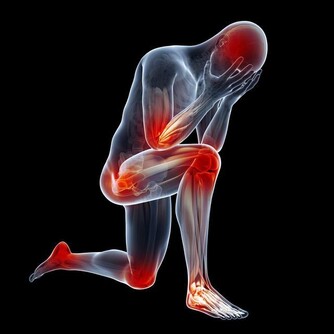

在日常生活和工作中,人們經常會被各種原因導致的“膝蓋”疼所困擾,並逐漸朝著年輕化發展,很多時候,往往因為疼痛程度小,時間段而被人們所忽視,並因此落下“病根”,為以後的生活帶來困擾,今天和大家一起掰扯掰扯那些被你忽略的膝蓋疼到底都是怎麼回事。

哪些常見的損傷會引起“膝蓋”疼?

1.軟組織損傷

軟組織損傷通常指皮膚、皮下、肌肉或是韌帶的損傷,主要原因是由於暴力引起的纖維結締組織撕裂所造成的,這種暴力主要是由於外界暴力或本身運動過度以及熱身不足產生,一旦出現損傷,會伴隨著皮膚、肌肉疼痛,乃至腫脹發生。